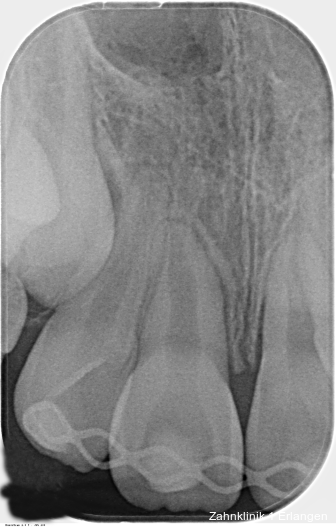

Zu den wesentlichen diagnostischen Verfahren, die zur Erfassung des Pulpastatus herangezogen werden, gehören neben der Inspektion und der röntgenologischen Bildgebung die Sensibilitätsprüfung sowie der Perkussionstest. Der Inspektion kommt insbesondere bei der Erstbehandlung eine wesentliche Rolle zu. Hierbei wird abgeklärt, ob es sich bei Zahnfrakturen um eine schmelzbegrenzte Verletzung handelt, ob das Dentin mitbetroffen und ob zusätzlich die Pulpa exponiert ist. Bei Dislokationsverletzungen wird das Ausmaß der Positionsveränderung erfasst und ob zusätzliche Gewebe wie Knochenstrukturen oder umliegende Weichgewebe betroffen sind. Auch können Farbveränderungen des Zahnes erfasst werden. Die Röntgendiagnostik zum Zeitpunkt des Unfalles gibt Aufschluss über die Größe des Pulpenkavums und das Lumen des Wurzelkanals, den Stand des Wurzelwachstums und die periapikalen Verhältnisse. Des Weiteren finden sich möglicherweise Hinweise auf eine Wurzelfraktur.

Zu den Zahnfrakturen mit Pulpabeteiligung gehören die in das Dentin reichende unkomplizierte Kronenfraktur sowie die komplizierte Kronenfraktur mit Pulpaexposition. Rein schmelzbegrenzte Frakturen sind hinsichtlich des Pulpastatus als unkritisch einzuschätzen.1 Dislokationsverletzungen betreffen die Pulpa insofern, als das Gefäß-Nerv-Bündel je nach Ausprägung der Positionsveränderung gestaucht, gedehnt oder abgerissen sein kann. Bei Zähnen mit abgeschlossenem Wurzelwachstum geht man davon aus, dass spätestens ab einer Dislokation von 2 mm die Pulpa abgerissen wurde, was die zeitnahe Einleitung der Wurzelkanalbehandlung notwendig macht.2, 3 Bei geringer ausgeprägter Dislokation kommt den Nachkontrollen eine wesentliche Rolle zu, bei denen jeweils dem Pulpastatus besonderes Augenmerk zukommen sollte, um eine Pulpanekrose frühzeitig zu detektieren.

Bei ausgeprägten Dislokationsverletzungen stellt die Schädigung des Parodonts die dominierende Verletzung dar, die auch zu Spätfolgen und Komplikationen führen kann. Verletzungen des Endodonts sind im Hinblick auf den Zahnerhalt vergleichsweise unbedeutender, da die Wurzelkanalbehandlung eine Infektion relativ sicher verhindern oder beseitigen kann. Die Erstversorgung schließt im Wesentlichen die Repositionierung und Schienung zur Ruhigstellung der betroffenen Zähne ein.3 Spätestens ab einer Positionsveränderung von 2 mm ist bei Zähnen mit abgeschlossenem Wurzelwachstum sicher von einem irreparablen Schaden der Pulpa auszugehen.2 Wichtig ist es, zeitnah, in der Regel während der Schienungsdauer, die Wurzelkanalbehandlung einzuleiten, um eine bakterielle Besiedelung des Wurzelkanals zu verhindern. Dabei reicht es zunächst aus, den Zahn zu eröffnen, desinfizierend zu spülen und eine medikamentöse Einlage einzubringen. Wird dies unterlassen, entwickeln sich bei entsprechender parodontaler Schädigung infektionsbedingte Resorptionen, die rasch fortschreiten und innerhalb relativ kurzer Zeit bis zum Zahnverlust führen können.